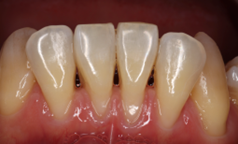

After

手術後4年経過

下顎前歯に顕著な歯肉退縮を認める

切開はEPPT(entire papilla preservation technique)

歯周基本治療後に根面被覆術を実施しその後はメンテナンス

歯肉退縮が生じることで知覚過敏に繋がるケースは少なくない。また将来的には根面う蝕の可能性も高くなるため、歯肉退縮している場合には予防的な観点から根面被覆手術をした方がいい場合がある。特に知覚過敏が強い場合にはブラッシングがしづらい場合も多くよりう蝕や歯周病のリスクが上がるため注意が必要と考える。